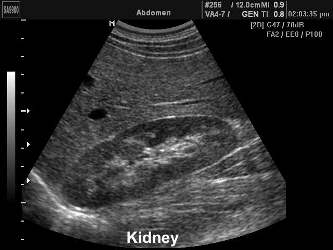

УЗИ почек и надпочечников

Ультразвуковое исследование почек позволяет оценить ткань почки,

прилежащих структур и почечных сосудов методом допплерографии.

Современная диагностика заболеваний почек невозможна без данной методики.